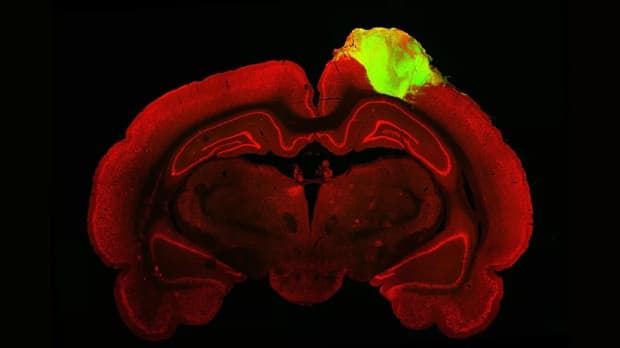

Para peneliti memetakan kondisi baru itu dengan menggunakan pelacak neon, yang mengungkapkan bahwa organoid telah berhasil terhubung ke retina melalui jaringan kabel ini. Terlebih lagi, para peneliti menunjukkan adanya rangsangan visual tikus terhadap lampu berkedip dan garis hitam dan putih di layar.

Kondisi itu berarti organoid yang ada di otak tikus melakukan respons seperti halnya yang terjadi saat korteks visual utuh. Percobaan kemudian ditingkatkan dengan menjalankan tes penglihatan atau perilaku pada tikus.